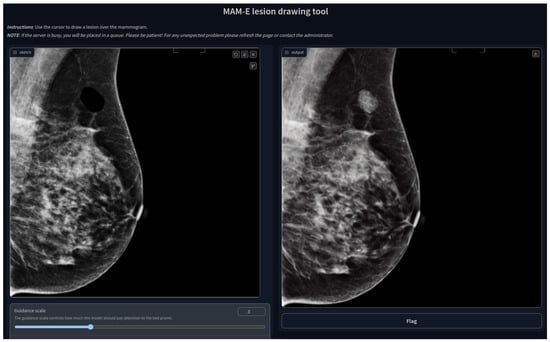

In the case of the inpainting task, the GUI has the option to upload the image that will be inpainted, although a default image is available. An interactive drawing brush is then activated, with which a lesion can be inpainted in any part of the mammogram, as shown in Figure 19.

Figure 19.

MAM-E lesion drawing tool.

We decided to build GUIs to make the pipelines of both tasks available to the public and easy to use. Our GUIs can run on remote servers and be accessible on the web thanks to GradIO, an open-source Python package for the rapid generation of the visual interface of ML models, by [36].

We developed five GUIs, one for each of our main diffusion pipelines. Two were designed for the conditional generation of mammograms of the original Siemens and Hologic datasets separately, with their own prompt characteristics. Similarly, one pipeline was created for the combination of both datasets, and it is presented as an example in Figure 1. In these three cases, the personalization options are set fixed and the user can only pick from the available options. Nevertheless, we added the option of a negative prompt, which allows the user to further personalize the generation.